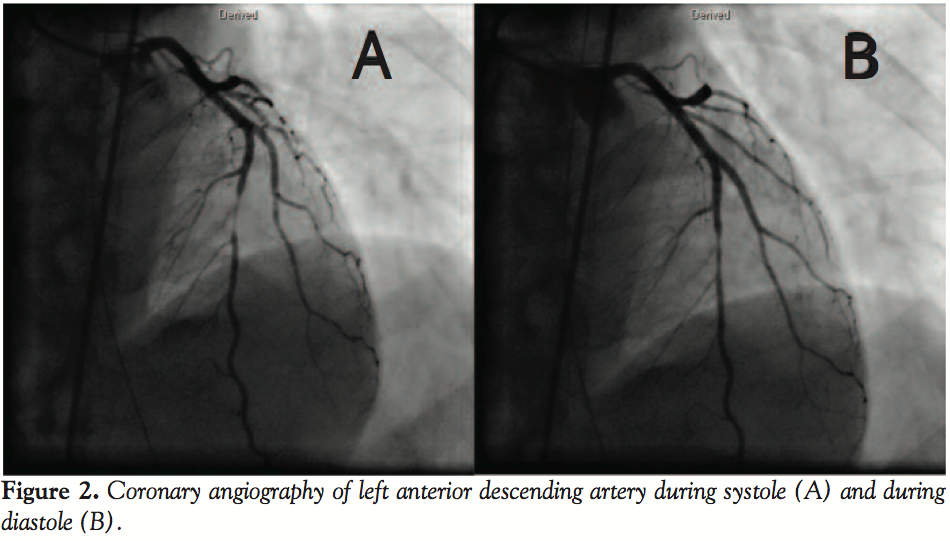

and performed emergent coronary angiography (CAG). CAG showed normal right coronary artery, left circumflex artery, and myocardial bridge at the mid-portion of the left anterior descending artery (Figures 2A and 2B). We had to confirm that the etiology of left ventricular wall motion abnormalities was not due to plaque rupture, but due to myocardial bridging, in order to decide further management. We applied OCT to render a decision. OCT showed smooth internal coronary artery wall at the bridge

and its proximal segment with no evidence of plaque rupture (Figure 3). We considered the possible contribution of coronary artery spasm to the etiology of ventricular fibrillation. We injected nicorandil and diltiazem intracoronarily and started 4 mg/H nicorandil intravenous infusion. Twenty minutes after infusion, the bridge dilated slightly. FFR was also measured by intracoronary adenosine, which was 0.82. We diagnosed the patient with

ventricular fibrillation caused by ST-elevation myocardial infarction (STEMI) due to myocardial bridging and focal spasm, with no clinically significant stenosis in the bridge lesion. We prescribed 200 mg Ca-antagonist, diltiazem, twice a day and 15 mg nicorandil 3 times a day. Clinical course, serial ECG findings, and late gadolinium enhancement MRI at day 5 were compatible with anterior STEMI (Figure 4D). Laboratory data were as follows: cardiac troponin T was 1.6 ng/mL on admission, and the peak serum creatine kinase level and creatine kinase MB isoenzyme were 421 IU/L and 47 IU/L, respectively, 10 H after symptom onset. Repeated coronary angiography at day 7 showed dilatation of the bridge (Figure 4A and 4B). Acetylcholine intracoronary injection induced focal stenosis at the same lesion without any symptoms and ECG changes (Figure 4C). We judged that no clinical ischemia could be induced with the medications. On day 8, the patient was discharged and remains well after 2 years.